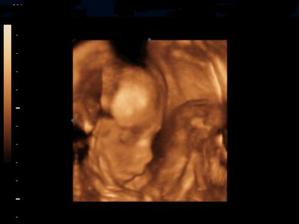

Naše kinderka

Dňa 24.8.2009 o 9.15 sa nám sekciou narodili naše krásne dvojičky Vanesska 2280 g a Larinka 2990 g. Robia nám veľkú radosť a moc ich ľúbime...